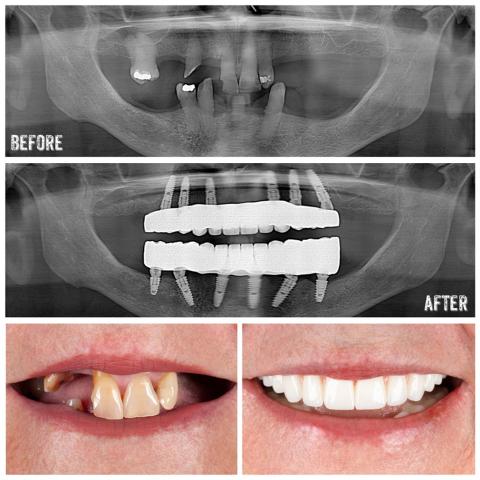

Dental Treatments